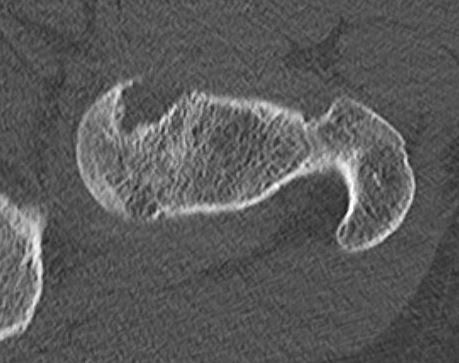

CT

CT periosteal chondromaCT periosteal chondroma